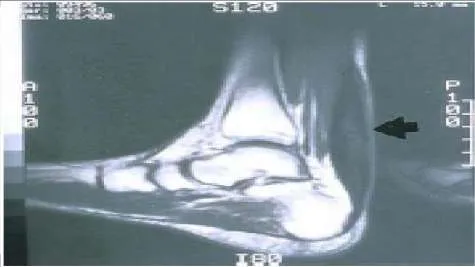

A 54-year-old woman presents for treatment of leg weakness. She is unable to walk up stairs. She recalls an injury to her ankle while playing tennis 1 year ago. Upon examination, she has poor plantarflexion strength, but excellent dorsiflexion and inversion strength. A magnetic resonance image of her leg is presented. The recommended treatment is:

This patient sustained a rupture of the Achilles tendon that went untreated for 1 year. She has symptomatic weak plantarflexion that may be improved by tendon transfer. Achilles repair is not possible due to the size of the defect. Although transfer of the peroneus brevis muscle or the flexor digitorum longus muscle has been described for correction of plantarflexion weakness, the flexor hallucis longus muscle is stronger and a better transfer.